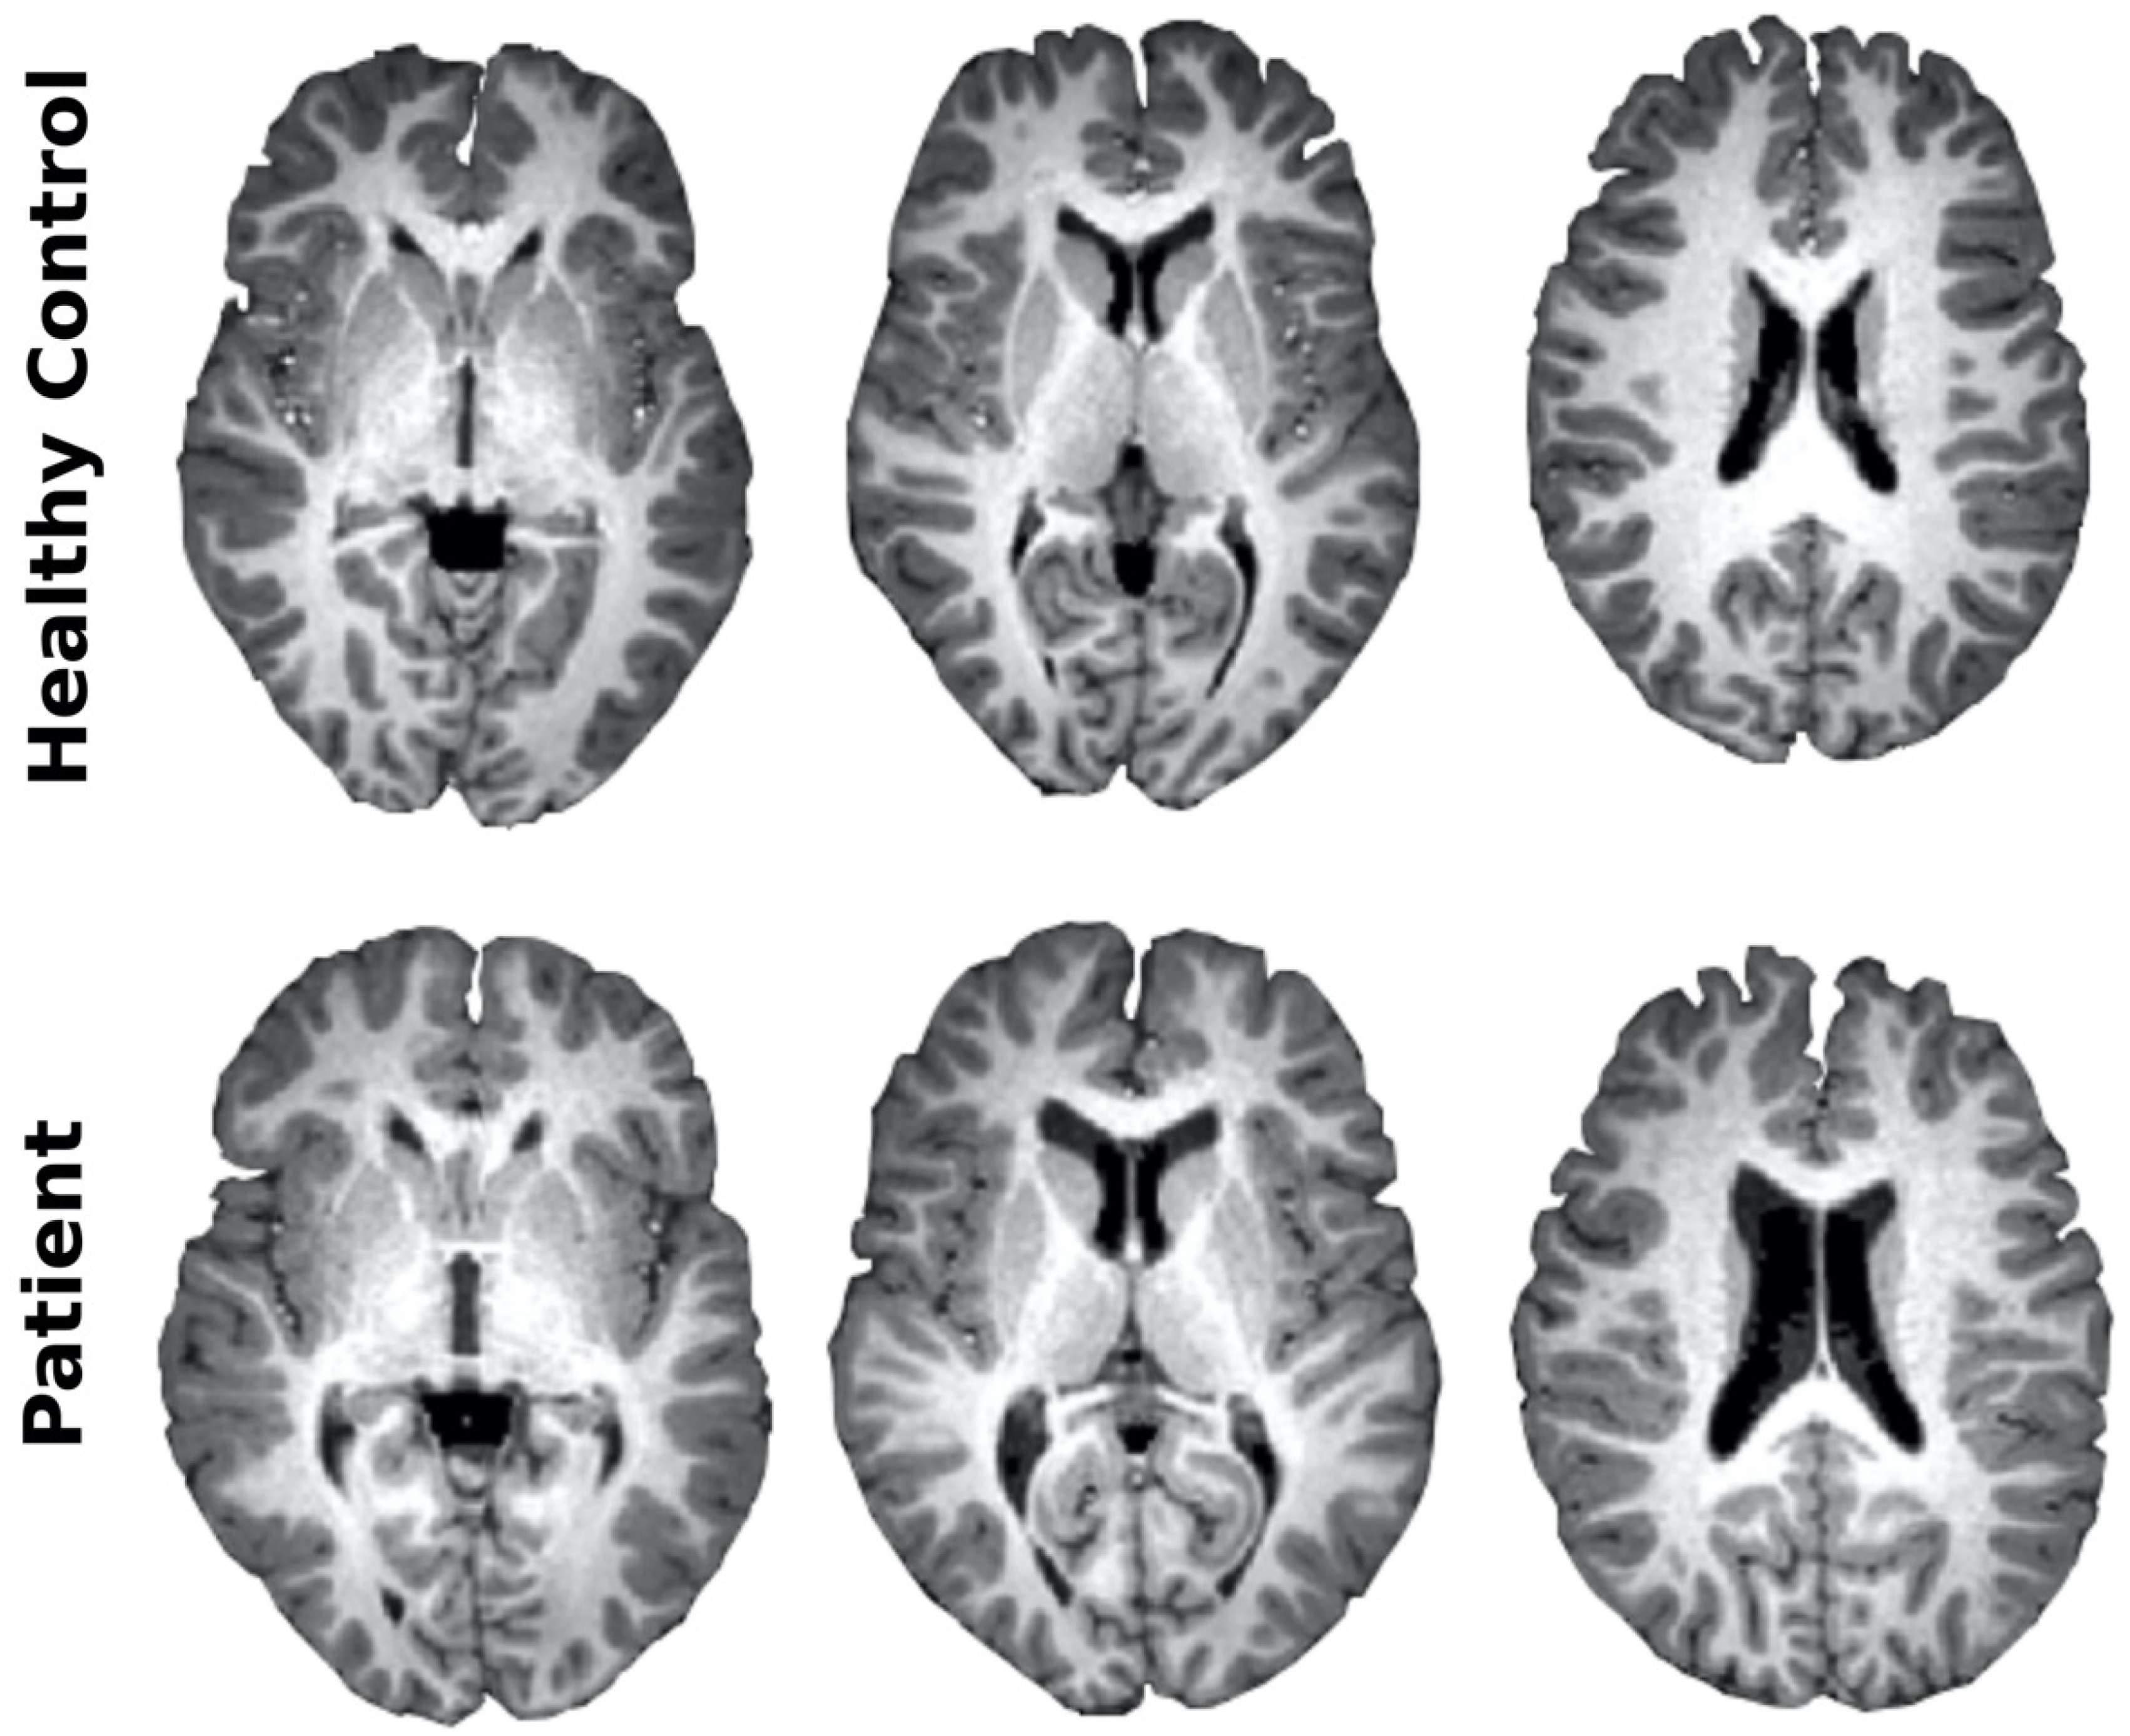

2.2. Magnetic Resonance Imaging

3.3. Imaging Characterization